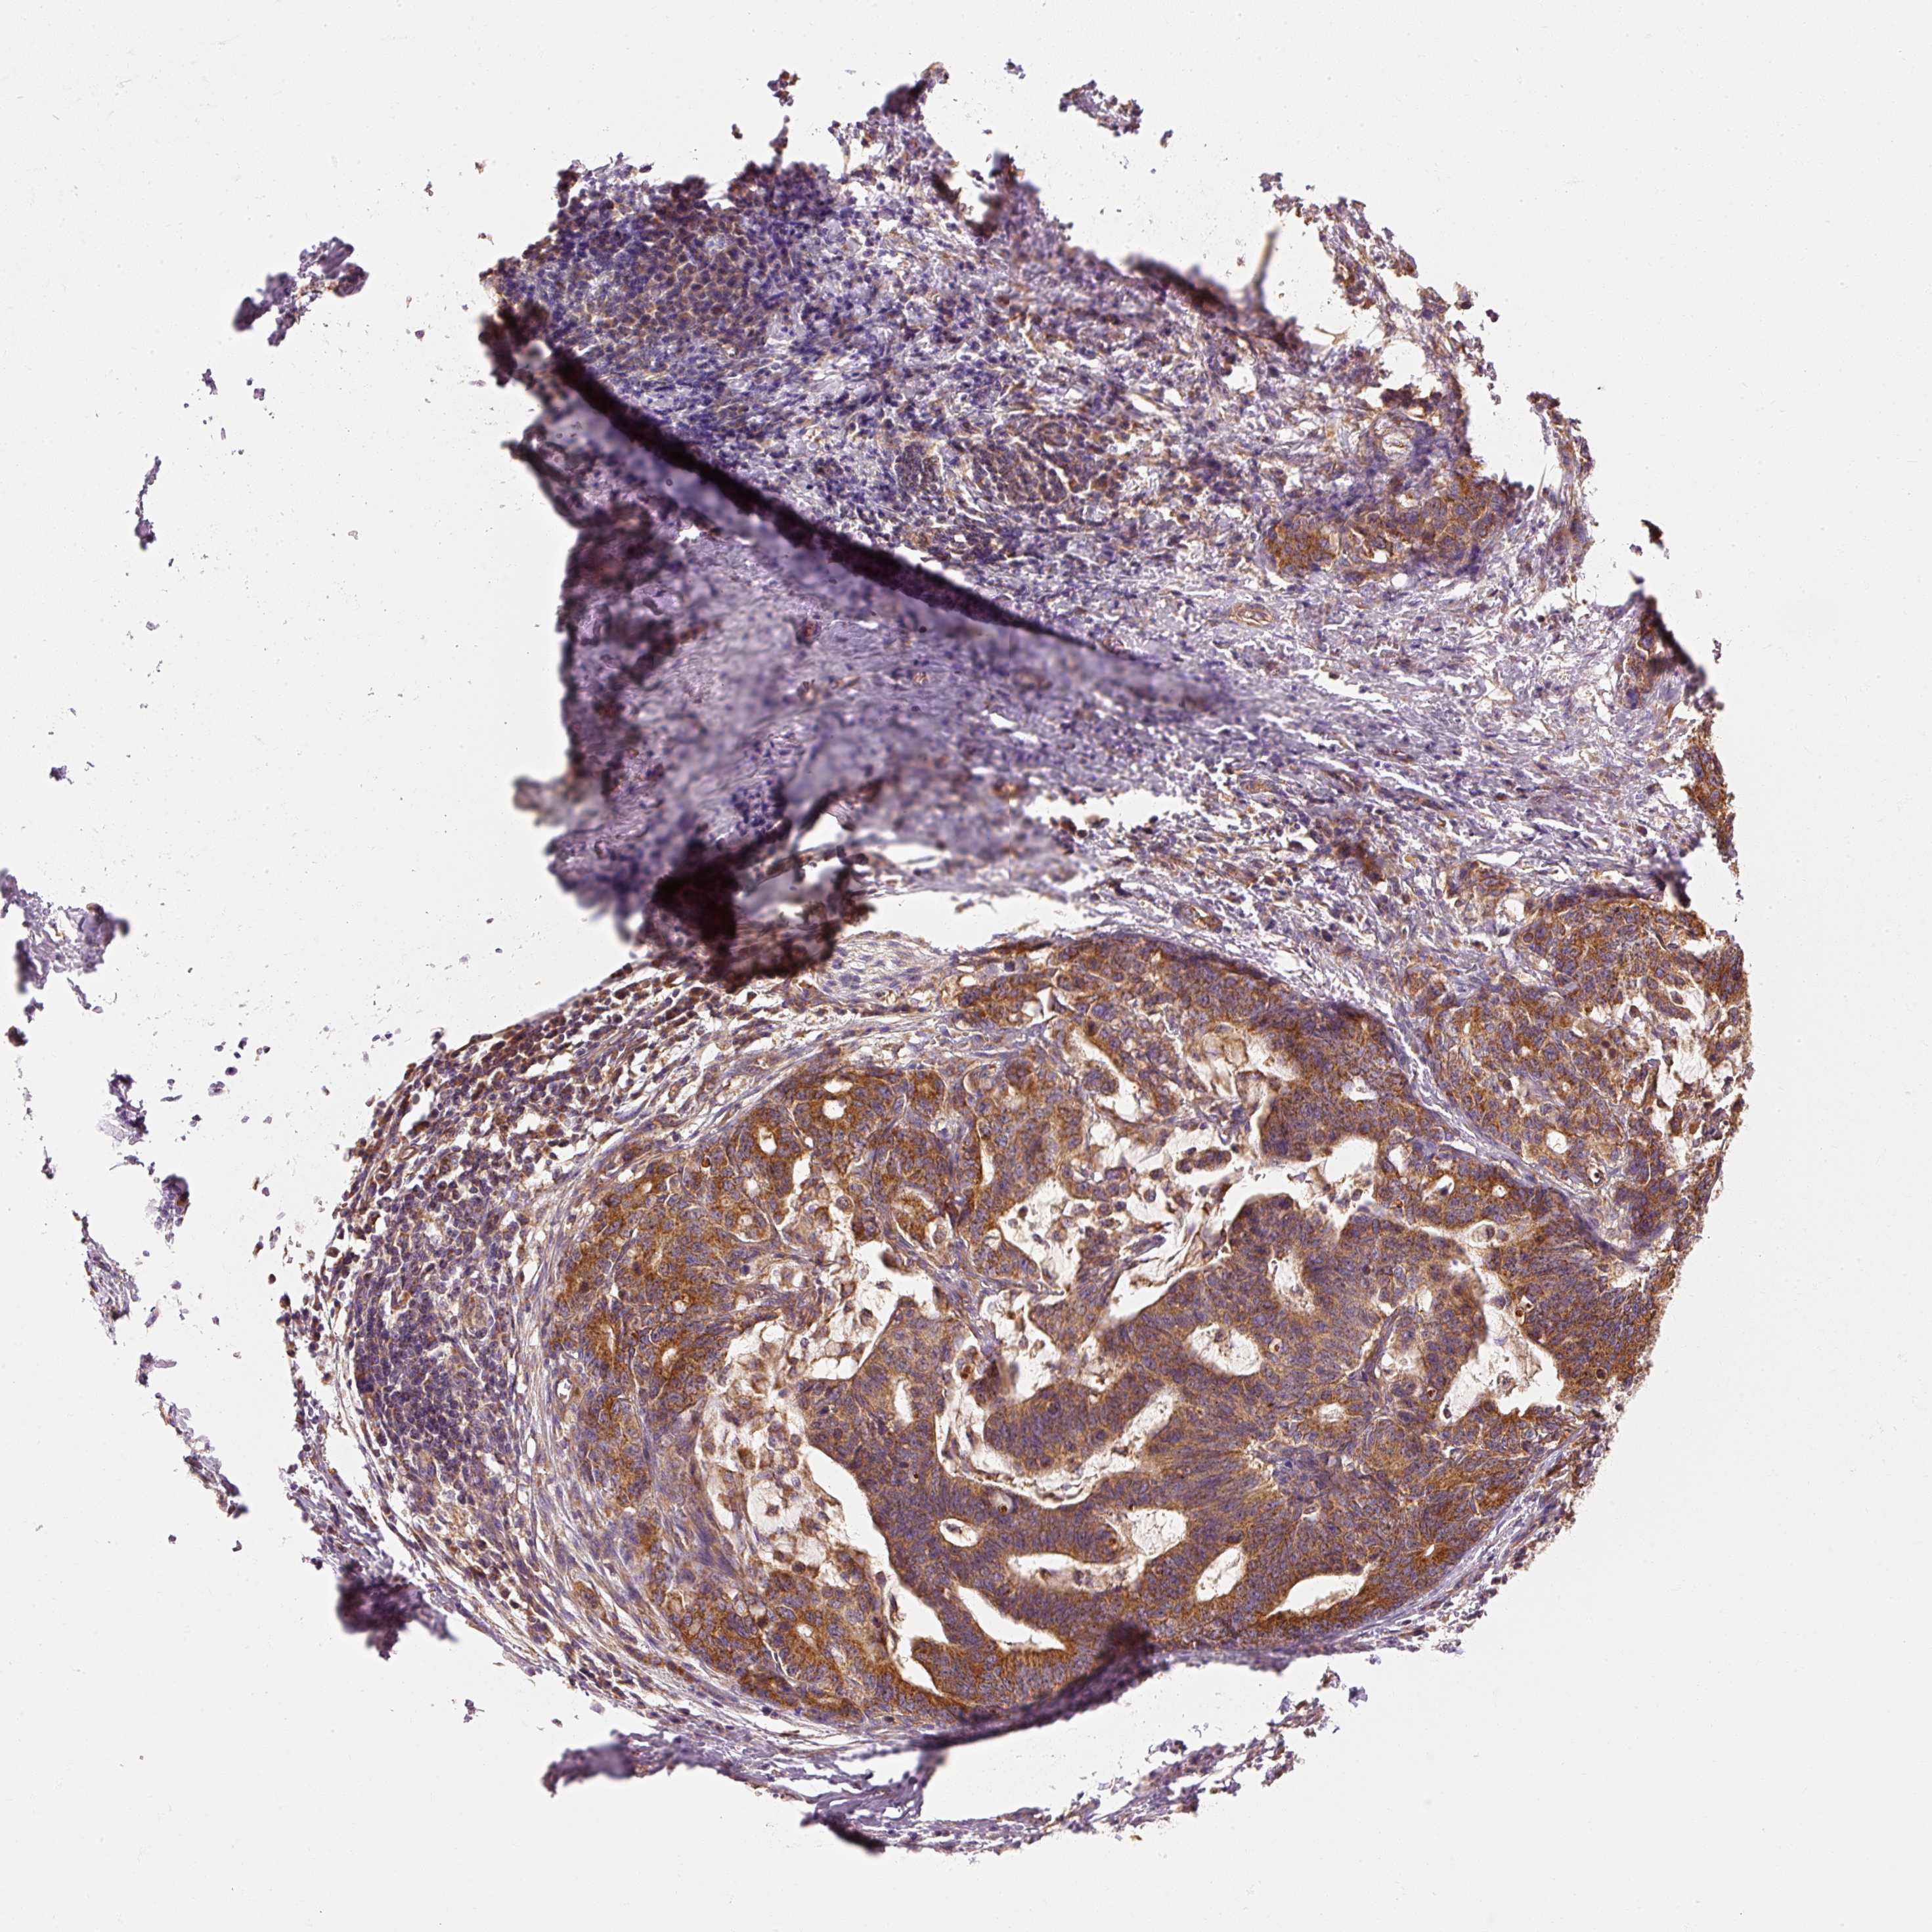

STOMACH CANCER - Protein expressioni

A mouse-over function shows sample information and annotation data. Click on an image to view it in a full screen mode. Samples can be filtered based on level of antibody staining by selecting one or several of the following categories: high, medium, low and not detected. The assay and annotation is described here.

Note that samples used for immunohistochemistry by the Human Protein Atlas do not correspond to samples in the TCGA dataset.

Antibody stainingi

Antibody staining in the annotated cell types in the current human tissue is reported as not detected, low, medium, or high, based on conventional immunohistochemistry profiling in selected tissues. This score is based on the combination of the staining intensity and fraction of stained cells.

Each image is clickable and will lead to virtual microscopy that enables deeper exploration of all samples and also displays staining intensity scores, fraction scores and subcellular localization as well as patient and tissue information for each sample.

Antibody HPA036231

Antibody HPA036232

Staining

High

Medium

Low

Not detected

Intensity

Strong

Moderate

Weak

Negative

Quantity

>75%

75%-25%

<25%

None

Location

Nuclear

Cytoplasmic/membranous

Cytoplasmic/membranous,nuclear

Adenocarcinoma, NOS